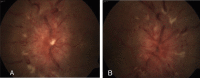

Behcet's disease is a multisystem vasculitis which can be associated with cerebral venous thrombosis (CVT) leading to increased intracranial tension and papilloedema. We report a case of a 17-year-old boy who presented to us with inward deviation of right eye with bilateral disc oedema and on further investigations was found to be Human Leukocyte Antigen (HLA) B5 positive, along with CVT on magnetic resonance venography which further led us to the diagnosis of non-parenchymal neuro-Behcet's.